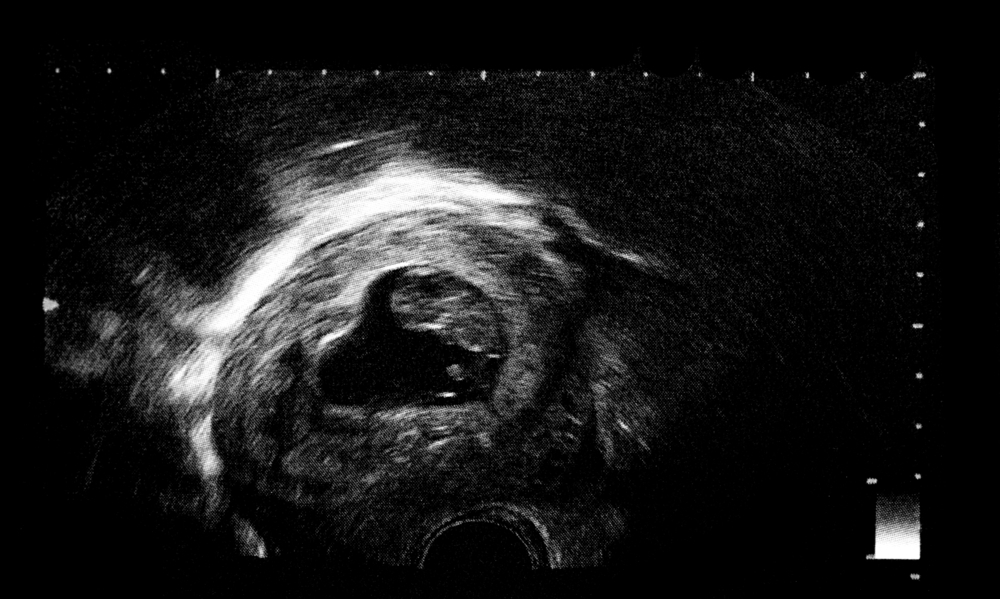

The 11th-week ultrasound is probably one of the most crucial scans throughout your pregnancy, so it is thoroughly advised to not miss this one. It gives you a glimpse of your baby for the first time, along with some other very important information.

"After completing 8 weeks, you will have an ultrasound scan. Most doctors ask for this scan around week 10. If the scan reveals nothing concerning and the baby is growing as expected, you have nothing to worry about. Listen to your body, and if you notice any concerning or warning signs, consult your doctor promptly. "